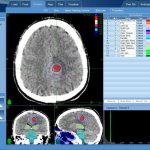

Контрастную миелографию в таком случае будут производить при помощи магнитно-резонансного томографа. Это предполагает обработку данных при помощи специального программного обеспечения. В результате будут получены трехмерные изображения, которые позволят обнаружить любые отклонения и патологические процессы в позвоночнике и спинном мозге.

Производится при помощи компьютерного томографа. Особенность заключается в том, что процедура предполагает исследование при помощи рентгеновского излучения. Это допустимо далеко не во всех случаях, поэтому решение будет принимать лечащий врач.

Современные магнитно-резонансные томографы позволяют сделать трехмерную (3D) реконструкцию области обследования. С помощью данной функции программного приложения сделать описание снимков легче, но следует знать нормальные анатомические особенности строения спинномозгового сегмента.

Схема контрастной цистернографии головного мозга (а) и мр-миелографии спинного мозга (б). Такие томограммы можно было получить на этапе начала применения магнитно-резонансной томографии в медицине. Постепенно технологии совершенствовались. Контрастная внутривенная МРТ позвоночника с 3D моделированием стала применяться несколько позднее.